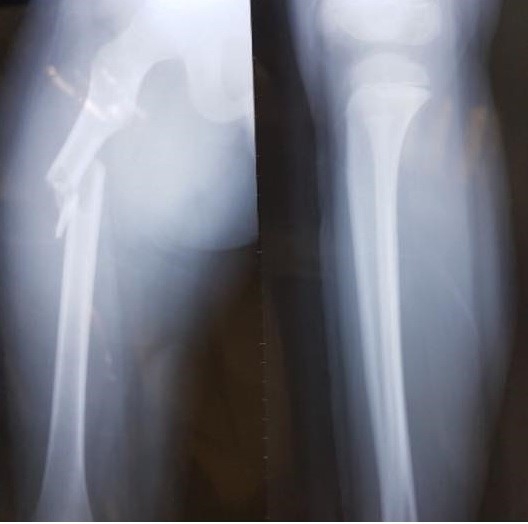

Ảnh chụp X-Quang chân cháu Kiên |

Trước đó, có 3 giáo viên, trong đó "mở màn" là giáo viên chủ nhiệm của em Trần Chí Kiên đã lên tiếng phản ứng mạnh mẽ với những nội dung mà hiệu trưởng đã báo cáo hoàn toàn sai sự thật.